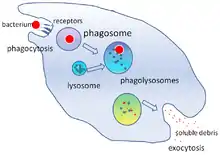

Under en infektion tiltrækkes fagocytter af kemiske signaler til steder, hvor patogenet har invaderet kroppen. Disse kemiske signaler kan komme fra bakterier eller fra andre fagocytter, der allerede er til stede. Denne metode at bevæge sig på kaldes kemotaksi. Når en fagocyt kommer i kontakt med en bakterie, vil receptorerne på fagocytens overflade binde sig til den, og bindingen vil medføre at fagocytten opsluger bakterierne. Denne proces kaldes fagocytose. Nogle fagocytter dræber det indtagne patogen med oxidanter og nitrogenoxid. Efter fagocytosen kan makrofager og dendritiske celler også deltage i antigenpræsentationen, en proces, hvor en fagocyt flytter molekylære brudstykker af det indtagne materiale tilbage på overfladen. Dette materiale vises derefter til andre celler i immunsystemet. Nogle fagocytter lokaliseres derefter til kroppens lymfeknuder og viser materialet til hvide blodlegemer kaldet lymfocytter. Disse processer er vigtig for at opbygge kroppens immunitet, jvf. immunsystemet.